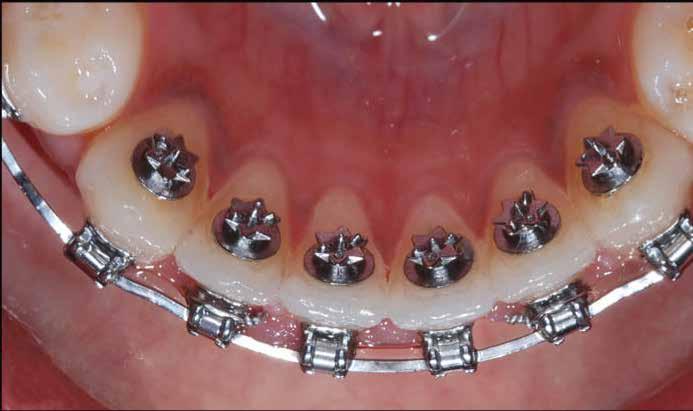

Szemfog becsiszolás

A szemfog elcsiszolásához piros gyémántfúró javasolt, finom szemcsézettséggel, 27-76 µm (okkluzálisan lekerekített – Rodentica, speciális hegyű 806314466514031, Komet 8833), gyorsítóval (max 160 000 fordulat/perc) megfelelő hűtés mellett, legalább 50 ml/perc. Ezt követi a felület kidolgozása és polírozása sárga gyémántcsiszolóval, extra finom szemcsézettséggel, 10-36 µm (Rodentica 806314466504031) és narancssárga Sof-Lex korongokkal (finom alumínium-oxid szemcsék 3-40 µm, extra finom, narancssárga-sárga, alumínium-oxid kristályok mérete 1,7 µm) könyökdarabban (25000 fordulat/perc) megfelelő hűtés mellett min. 50 ml/perc (2. a-d. ábra).

A javasolt eszközhasználati sorrend a következő: piros gyémántfúró (finom 27-76 µm), sárga gyémántcsiszoló (extra finom, 10-36 µm) gyorsítóban megfelelő hűtéssel (5,6 ábra.). Alkalmazhatunk gyémántkorongokat vagy oszcilláló mozgásokat végző korongokat is. A polírozást Sof-Lex korongokkal vitelezzük ki (finom-narancssárga 3-40 µm, extra finom – narancssárga-sárga, 1-7 µm), [43,33], (7. a-b ábra). Az approximális felszínek elcsiszolása több lépésben történik megfelelő vízhűtés alkalmazásával és helyi fluoridálással.

5. a-e ábra: A szemfog proximális éleinek beállítása rövidebb tűláng gyémántfúróval (Rodentica 465), továbbá hosszú tűkkel a-gyémánt láng (Rodentica 249) és hegyes láng gyémántfúróval (Rodentica 540). A braketeket már eltávolították ezekről a fogakról. 7. a-b. ábra: Polírozás narancssárga Sof-Lex koronggal.